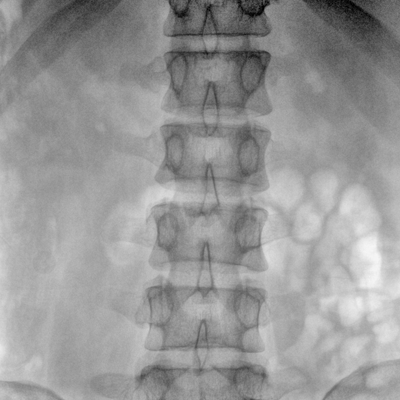

大尺寸動態(tài)平板探測器,高DQE、低噪聲、圖像清晰。采用多分辨率圖像增強(qiáng)處理技術(shù),不同部位不同圖像處理算法,滿足客戶多樣化的需求。

采用智能變頻脈沖透視技術(shù),優(yōu)化圖像質(zhì)量的同時降低輻射劑量,呵護(hù)醫(yī)患健康